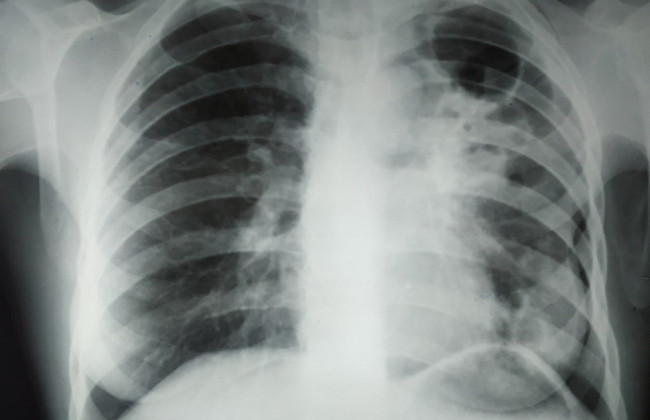

В Украине пока не наблюдается рост заболеваемости туберкулезом, который прогнозировали в связи с полномасштабной войной. В то же время фиксируются первые случаи внелегочного туберкулеза. Об этом сообщил генеральный директор Центра общественного здоровья Владимир Курпита.

По его словам, несмотря на опасения по поводу резкого повышения уровня заболеваемости после окончания войны, таких тенденций в настоящее время не зафиксировано. Однако появление случаев внелегочного туберкулеза может свидетельствовать о необходимости подготовки системы здравоохранения к новым вызовам.

«Все нас пугают, что после окончания войны, например, может расти заболеваемость туберкулезом. Мы не видим сейчас этих тенденций, но мы видим, например, первые признаки того, что у нас появляются случаи так называемого внелегочного туберкулеза. Это может свидетельствовать о том, что нам нужно готовиться к этой истории», — отметил Курпита.